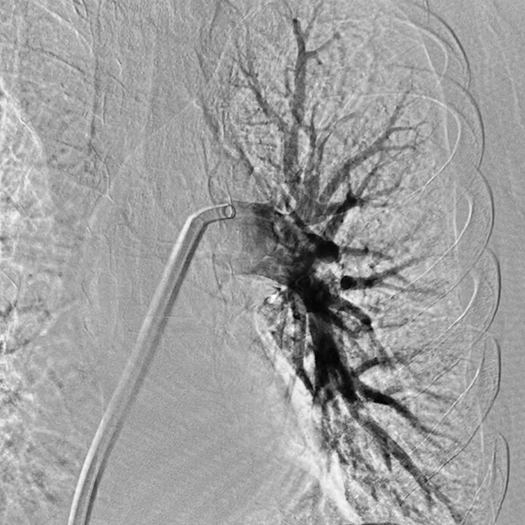

Pulmonary Embolism Cases

Venous Cases

Images used with permission and provided for illustrative purposes only. Procedural techniques and decisions based on physician’s medical judgment. Individual results may vary. Consents on file at Penumbra, Inc.